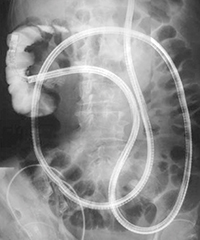

И именно в таких случаях помочь гастроэнтерологу и хирургу призвана еще более современная методика — двухбаллонная энтероскопия, называемая на Запа-

де еще «Push-and-Pull-Enteroskopie» (PPE). Уже из названия становится понятным и сам принцип этого предложенного в 2001 г. японцами (Yamamoto H. et al., 2001) и впервые в 2003 г. примененного на Западе исследования. Передвижение по тонкому кишечнику телескопически выдвигаемого зонда длиной около двух метров, состоящего из непосредственно энтероскопа и наружного зонда большего диаметра, осуществляется путем «нанизывания» на эндоскоп кишки, что становится возможным за счет периодического раздувания и перемещения относительно друг друга двух баллонов, один из которых находится непосредственно на конце эндоскопа, а другой — на конце наружного зонда. Так как по структуре своей двухбаллонный энтероскоп является обычным эндоскопом, он обладает и всеми его

преимуществами — возможностью промывать оптику во время исследования (что особенно ценно при диагностике кровотечений), проводить биопсии и, самое главное, осуществлять эндоскопические вмешательства. Именно поэтому зачастую капсульная эндоскопия (естественно, при положительном результате) дополняется двухбаллонной энтероскопией. Введение энтероскопа, как правило, осуществляется перорально ортоградно, только в редких случаях (например, при недостаточной инспекции кишечника или выявленной во время капсульной эндоскопии локализации источника кровотечения в дистальных отделах тонкого кишечника) необходимо дополнительное проведение ретроградной трансанальной энтероскопии. Длительность исследования составляет в среднем два часа, естественно, без внутривенного наркоза (как правило, хватает обычной седоанальгезии) тут не обойтись.